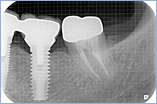

現在はインプラント治療は一般的に行われています。

治療中はムシ歯の治療など使用している局所的な麻酔で行えます。ほとんどの場合可能ですが専門医がくわしく診断し最善の方法をおすすめします。

※インプラントをより長くお使いいただくために定期的にクリーニングに来ていただき状態をチェックさせていただきます。

インプラント

¥280,000(被せ物は除きます)

※消費税は別にかかります。